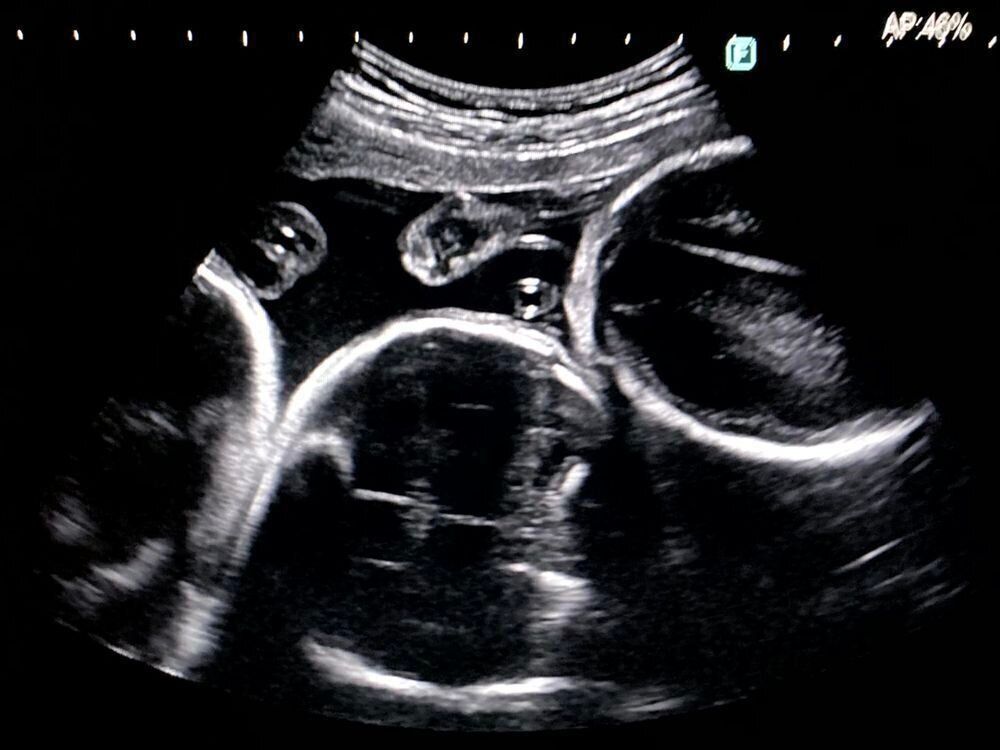

そしたら、ありがたいことに1度の体外受精で陽性反応が出たんです!まだまだ安心できないとは思いながらも、すごくうれしかったですね。そこから心拍を確認するために、2週間後に再受診することになって、夫もそのときはエコーを見る部屋に一緒に入りました。

すると、エコーを見ていた先生が急に『ヒンタイかもしれない』ってつぶやいて、もう1人の先生を呼びに行かれたんです。『ヒンタイ』って聞きなれない言葉だし、私はおなかの子に何かあったのかなと思ってすごく不安になり、夫も『えっ?』って不安そうな顔をしていたんですね。

そして、医師2人で診てもらったら、『これは三つ子かもしれないね』って。

その言葉で、不安な気持ちが一気に吹き飛んで『ええっ!』って驚いちゃって、思わず笑ってしまいました。心配事があるのかと思ったら、1人増えた!みたいな感じ(笑)。問題ないなら、よかった!って。だから、三つ子だと初めて知ったときは、とにかく驚きとホッとした気持ちが大きかったですね。ちなみに、三つ子のことを『品胎』と言うんだそうです。